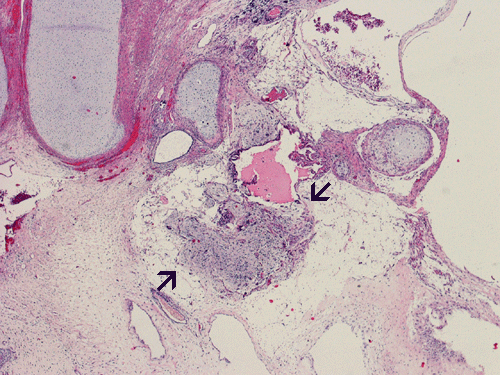

The entire specimen was submitted for histologic examination. The bulk (over 99%) of the tumor was composed predominantly of mature intestinal elements (Panel A, B, and C) and skin, respiratory type mucosa, cartilage, and small amount of mature neural parenchymal tissue of the central nervous system (Panel D and E). Neither immature nor malignant elements are present. Small microscopic foci of well demarcated, neural parenchymal tissue with increased atypia (arrow in panel F) are noted. On higher magnification (Panel G and H), these areas contain large, bizarre appearing cells with dark chromatin but no prominent nucleoli. There are also scant multinucleated cells and mineralized substances (arrow in Panel H). Another example of these foci is illustrated in Panel I, J, and K. These atypical foci comprised less than 1% of the volume of the tumor. They are all microscopic in size and show no evidence of expansion or invasion into the surrounding tissue.

The foci of neural parenchymal tissue with atypia raised the concern for malignancy. The atypical foci are all microscopic in size and well demarcated. They do not invade into the adjacent tissue. Although large atypical nuclei are noted, there is no prominent nucleoli. These changes are more consistent with ancient changes (degenerative atypia) or resulted from the chemotherapy prior to the resection. Identification of mineralized tissue is an additional features to confirm the benign biological potential of these foci. These foci are atypical but not embryonal and must be distinguished from immature element. With this token, the tumor is a mature teratoma but not an immature teratoma. Please see the discussion below for growing teratoma syndrome. This case is also unusual for an elevated alpha fetal-protein in serum with a lack of yolk sac tumor component in the tumor. Please see the discussion below for discussion.